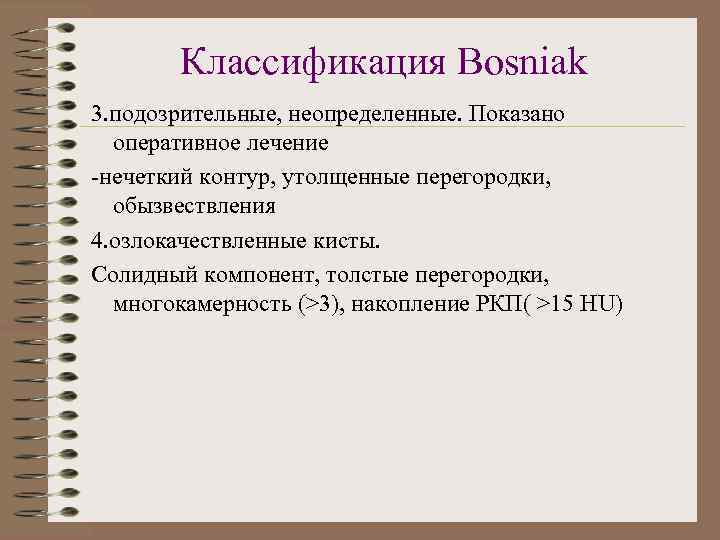

Классификация Bosniak 3. подозрительные, неопределенные. Показано оперативное лечение -нечеткий контур, утолщенные перегородки, обызвествления 4. озлокачествленные кисты. Солидный компонент, толстые перегородки, многокамерность (>3), накопление РКП( >15 HU)